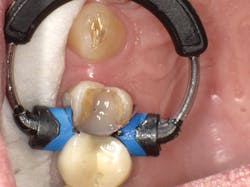

In Case Two, we'll replace an old composite inlay (figure 6). As in the first case, the LiteTouch erbium YAG laser was used to remove the inlay without anesthetic. As the decay had spread subgingivally on the interproximal surface, a small gingivectomy was needed to access the final gingival margin. After placing some topical anesthetic on the soft tissue and using a low energy setting, the Lite Touch laser was used to remove the excess interproximal soft tissue (figure 7). A sectional matrix band and newly designed Fusion Wedge (Garrison) was placed, and the band lightly burnished against the adjacent tooth (figure 8). A self-etch adhesive technique using Futurabond U was used. After curing the adhesive, a bulk-fill flowable (x-tra base, Voco) was used in the floor of the box. Using a flowable bulk fill in this fashion virtually assures you of a tight gingival seal at the bottom of the proximal box. Next, Admira Fusion Opaque shade OA3 was used to mimic the dentin (figure 9), followed by placement of the final enamel layer of material. The finished restoration exhibits a high polish with a close-up intraoral appearance that mimics a ceramic inlay (figure 10).

Figure 6

Figure 7

Figure 8

Figure 9

Figure 10